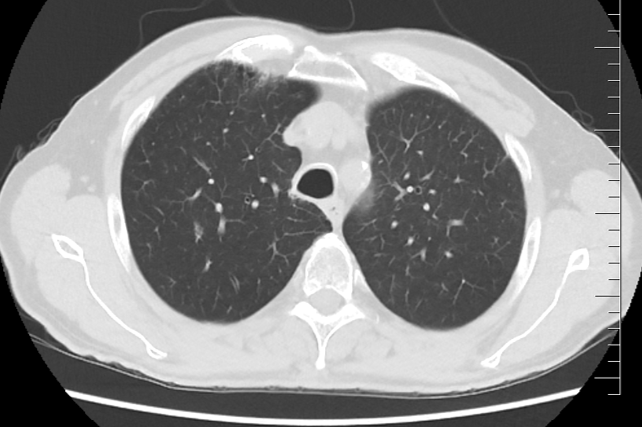

Řez plicemi z CT screeningu: Kontrolní  CT plic po 2 sériích léčby pembrolizumabem v 1/2022.

Obr 3. – Kontrolní  CT plic po 2 sériích léčby pembrolizumabem v 1/2022.